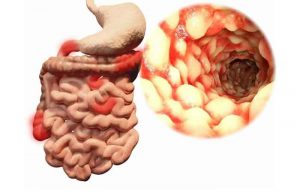

بیماری کرون چیست؟ + علت، علائم و راه های درمان

11 دقیقه